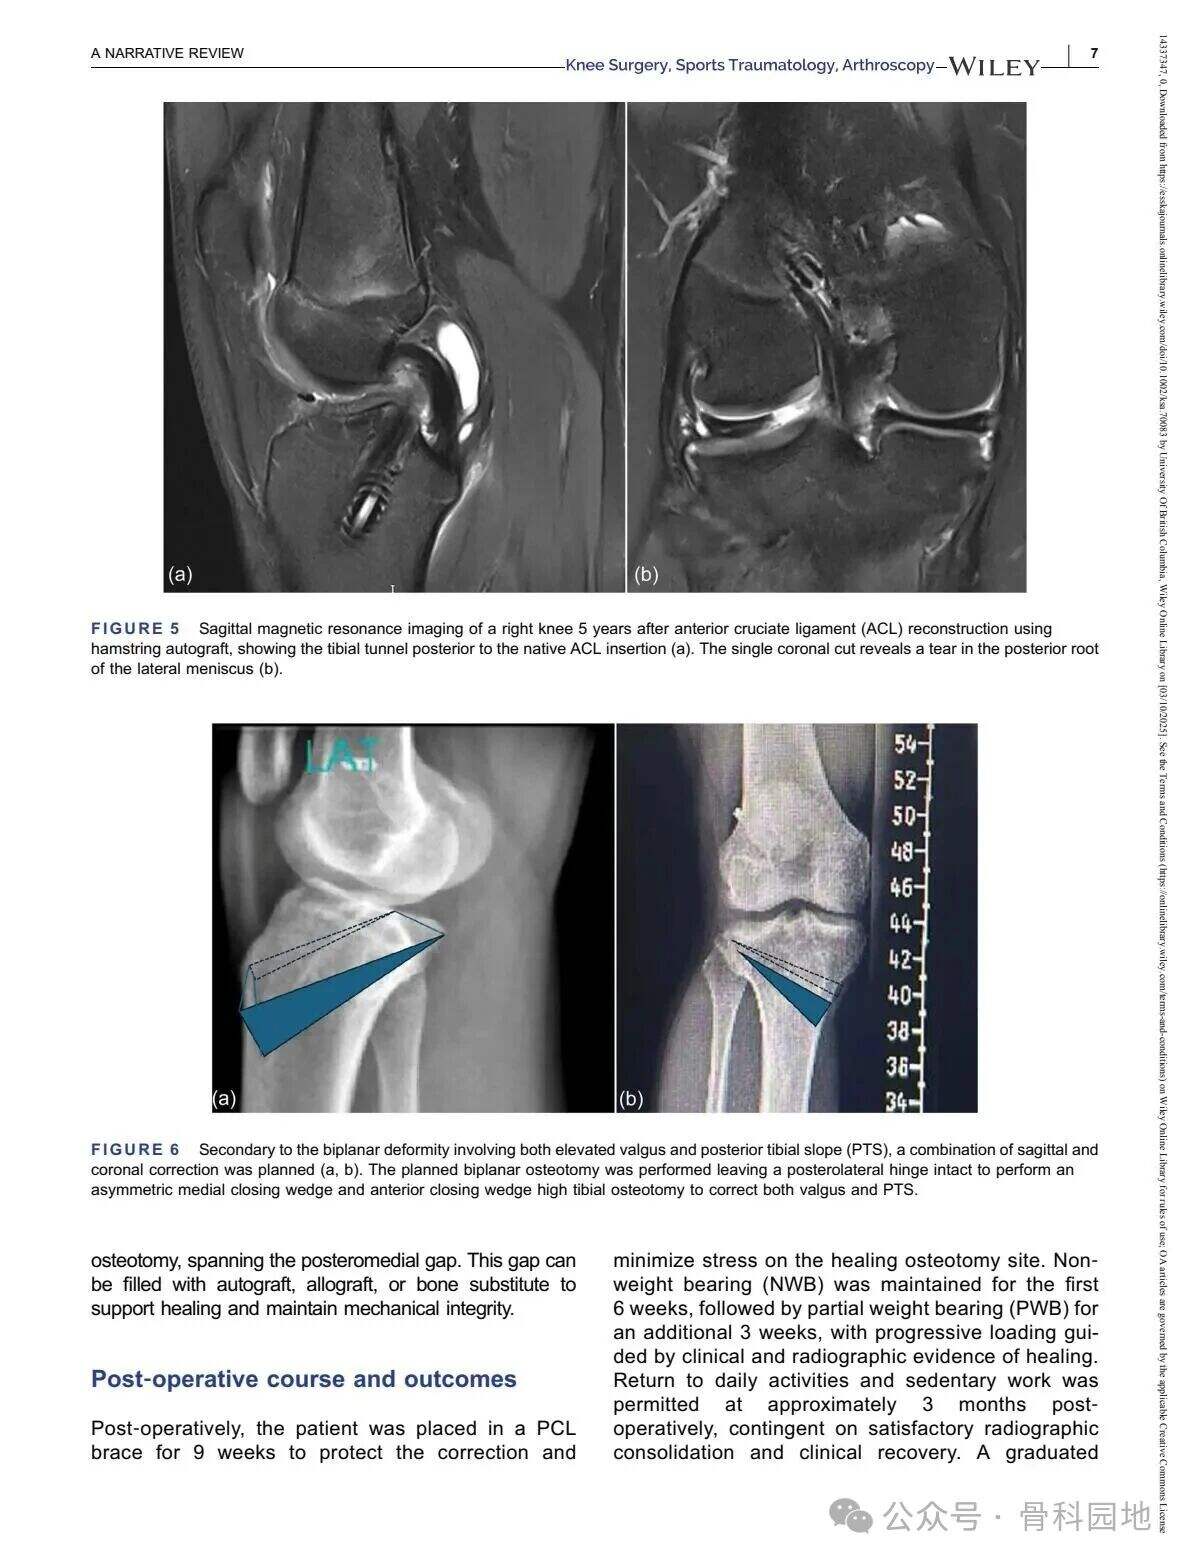

Čeprav konvencionalna visoka tibialna osteotomija (HTO) predvsem obravnava nepravilno poravnavo v koronalni ravnini, pomembnost poravnave v sagitalni ravnini – zlasti posteriornega tibialnega naklona (PTS) – ni mogoče prezreti v primeru nesposobnosti križnih vezi. Kombinirane nepravilnosti v koronalni in sagitalni ravnini so razmeroma redke in predstavljajo posebne kirurške izzive. Ta narrativni pregled povzema ustrezno literaturo ter predstavlja tehnične strategije za obravnavo zapletenih dvoravninskih nepravilnosti s pomočjo primerov iz prakse in razprav o različnih tehnikah.